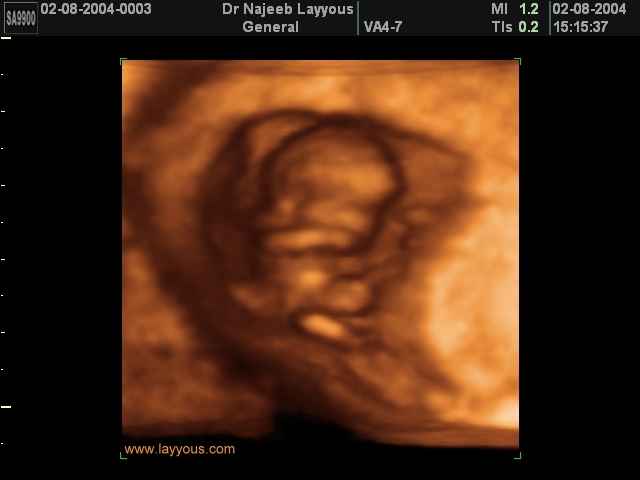

3D First Trimester Ultrasound Scan Photos ( Early Pregnancy Ultrasound Photos ) | Dr N Layyous